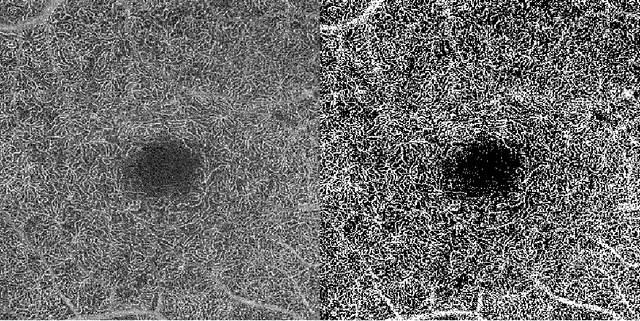

Abstract:Purpose: Optical Coherence Tomography Angiography (OCT-A) permits visualization of the changes to the retinal circulation due to diabetic retinopathy (DR), a microvascular complication of diabetes. We demonstrate accurate segmentation of the vascular morphology for the superficial capillary plexus and deep vascular complex (SCP and DVC) using a convolutional neural network (CNN) for quantitative analysis. Methods: Retinal OCT-A with a 6x6mm field of view (FOV) were acquired using a Zeiss PlexElite. Multiple-volume acquisition and averaging enhanced the vessel network contrast used for training the CNN. We used transfer learning from a CNN trained on 76 images from smaller FOVs of the SCP acquired using different OCT systems. Quantitative analysis of perfusion was performed on the automated vessel segmentations in representative patients with DR. Results: The automated segmentations of the OCT-A images maintained the hierarchical branching and lobular morphologies of the SCP and DVC, respectively. The network segmented the SCP with an accuracy of 0.8599, and a Dice index of 0.8618. For the DVC, the accuracy was 0.7986, and the Dice index was 0.8139. The inter-rater comparisons for the SCP had an accuracy and Dice index of 0.8300 and 0.6700, respectively, and 0.6874 and 0.7416 for the DVC. Conclusions: Transfer learning reduces the amount of manually-annotated images required, while producing high quality automatic segmentations of the SCP and DVC. Using high quality training data preserves the characteristic appearance of the capillary networks in each layer. Translational Relevance: Accurate retinal microvasculature segmentation with the CNN results in improved perfusion analysis in diabetic retinopathy.

Abstract:Automatic quantification of perifoveal vessel densities in optical coherence tomography angiography (OCT-A) images face challenges such as variable intra- and inter-image signal to noise ratios, projection artefacts from outer vasculature layers, and motion artefacts. This study demonstrates the utility of deep neural networks for automatic quantification of foveal avascular zone (FAZ) parameters and perifoveal vessel density of OCT-A images in healthy and diabetic eyes. OCT-A images of the foveal region were acquired using three OCT-A systems: a 1060nm Swept Source (SS)-OCT prototype, RTVue XR Avanti (Optovue Inc., Fremont, CA), and the ZEISS Angioplex (Carl Zeiss Meditec, Dublin, CA). Automated segmentation was then performed using a deep neural network. Four FAZ morphometric parameters (area, min/max diameter, and eccentricity) and perifoveal vessel density were used as outcome measures. The accuracy, sensitivity and specificity of the DNN vessel segmentations were comparable across all three device platforms. No significant difference between the means of the measurements from automated and manual segmentations were found for any of the outcome measures on any system. The intraclass correlation coefficient (ICC) was also good (> 0.51) for all measurements. Automated deep learning vessel segmentation of OCT-A may be suitable for both commercial and research purposes for better quantification of the retinal circulation.